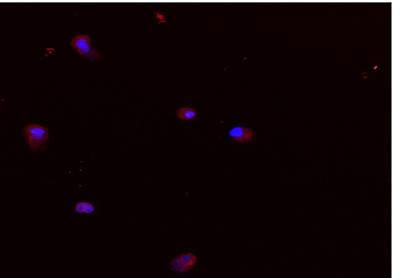

In laboratory tests, the researchers used gold nanoparticles – tiny spherical particles made up of thousands of gold atoms – coated with oligonucleotides (strands of DNA), to optically detect the specific messenger RNA (mRNA) signatures of skeletal stem cells in bone marrow. When detection takes place, the nanoparticles release a fluorescent dye, making the stem cells distinguishable from other surrounding cells, under microscopic observation. The stem cells can then be separated using a sophisticated fluorescence cell sorting process.

Professor Oreffo said: “Skeletal stem cell based therapies offer some of the most exciting and promising areas for bone disease treatment and bone regenerative medicine for an aging population. The current studies have harnessed unique DNA sequences from targets we believe would enrich the skeletal stem cell and, using Fluorescence Activated Cell Sorting (FACS) we have been able to enrich bone stem cells from patients. Identification of unique markers is the holy grail in bone stem cell biology and, while we still have some way to go; these studies offer a step change in our ability to target and identify human bone stem cells and the exciting therapeutic potential therein.”

“In this research project, we designed nanoparticles coated with short sequences of DNA, which are able to sense HSPA8 mRNA and Runx2 mRNA in skeletal stem cells and together with advanced FACS gating strategies, to enable the assortment of the relevant cells from human bone marrow.

“An important aspect of the nanomaterial design involves strategies to regulate the density of oligonucleotides on the surface of the nanoparticles, which help to avoid DNA enzymatic degradation in cells. Fluorescent reporters on the oligonucleotides enable us to observe the status of the nanoparticles at different stages of the experiment, ensuring the quality of the endocellular sensor.”